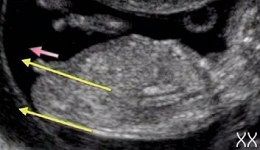

А вот девочка

Пол малышаДевочки у кого мальчики, на фото так выглядит или нет? Нам вчера сказали что мальчик а я сомневаюсь почему-то.

Вроде видно приборчик))) На таком сроке уже хорошо видно, нам вот пока на узи все показывали так мы сразу увидели что у нас парень)

Ну знаете мне в 15нед. показали нашу "прелесть" и прям хорошо было видно именно пирожочек))Так,что думаю,что мальчик!